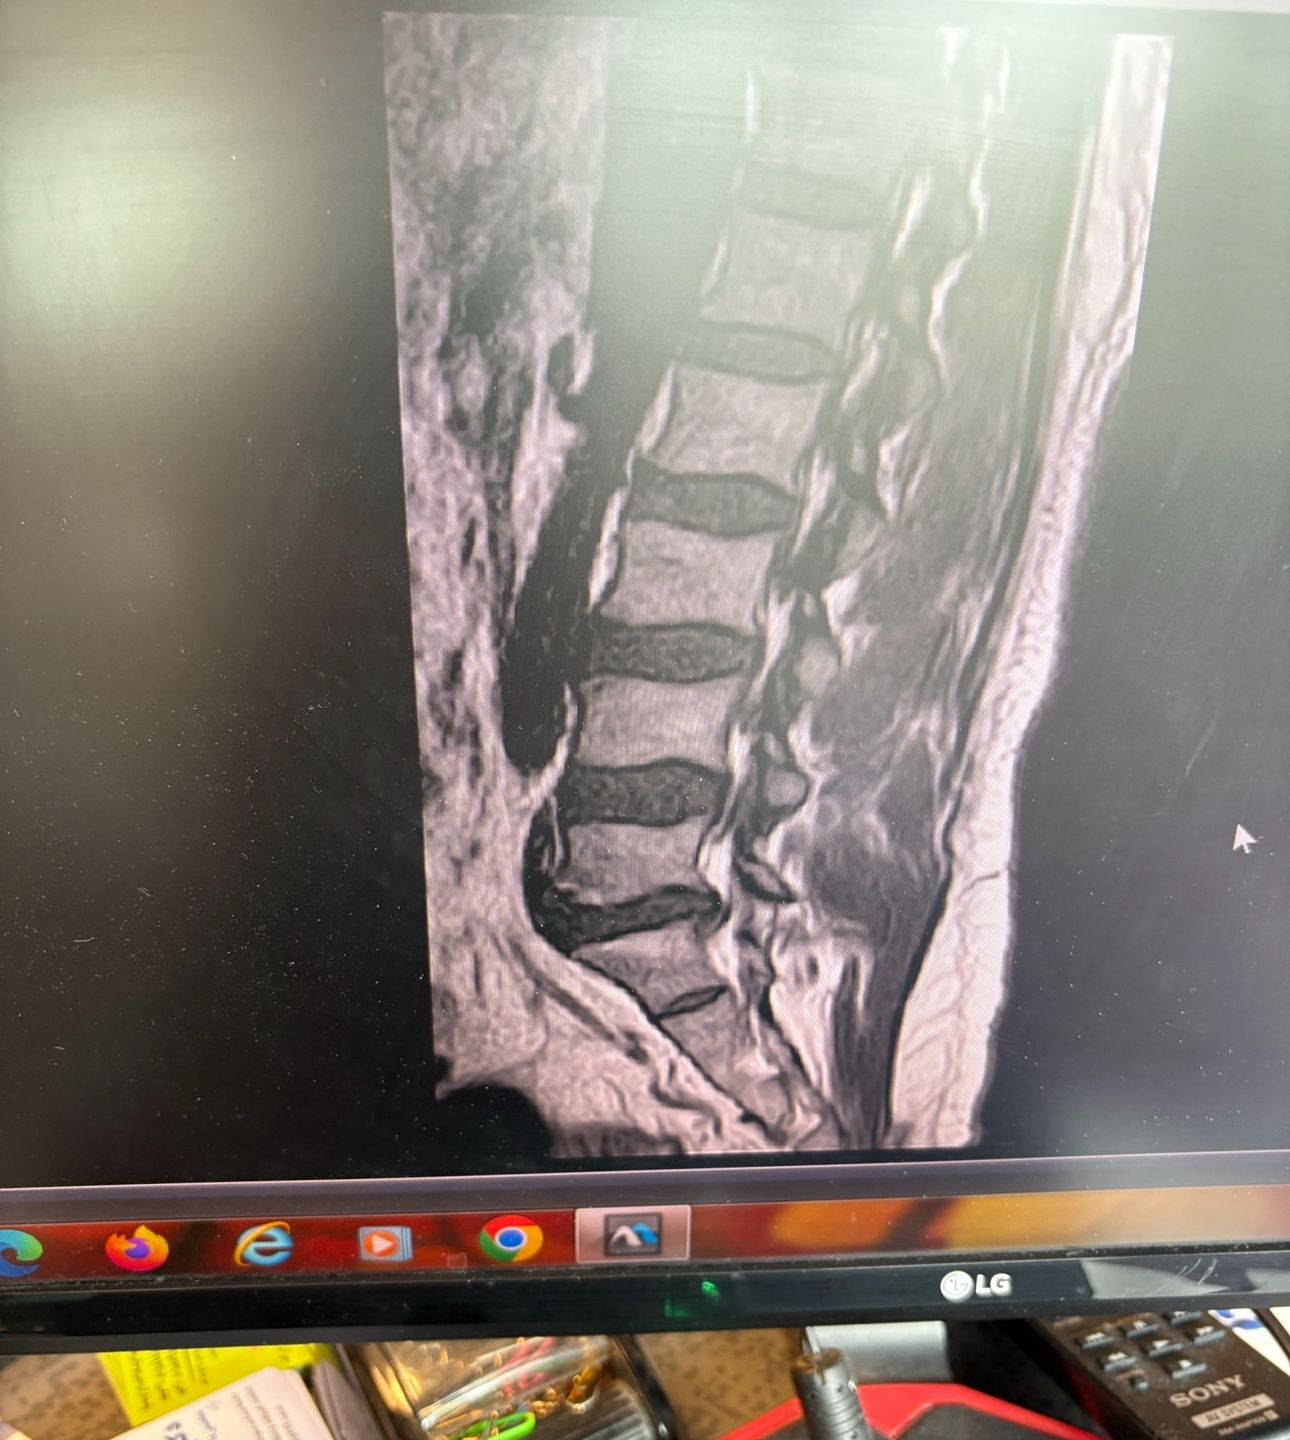

46 years old female patient presented to my clinic yesterday june 1/2025 with LBP and radicular L leg pain for several months which hasn’t responded to physio 2 neurosurgeons have visited her and didn’t suggest any surgery Neurological exam was unremarkable please see her mri/ emg/ncv and her huge tarlov cyst and possible L IVF L4-5 hyperbulge I ordered sacrum mri and ct scan and new emg/ncv and asked her with her sacral Ct scan and MRI first sees another two famous neurosurgeons and see if that large cyst is the reason for her pain if not i can work on her L4-S1 area Do you think her radicular pain can originate from her large cyst in sacrum? Do you consider surgery and removing her sacral cyst?